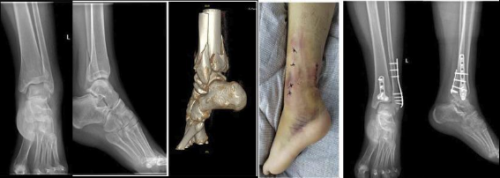

据庄全魁介绍,《四肢骨折微创治疗新技术(STMIPO)》是对微创接骨板技术(MIPO,即Minimally invasive plate oseoynthesis)的创新,MIPO最先用于治疗胫骨远端及股骨远端的骨折,距今已有30余年。因该技术不破坏骨膜血供,间接复位骨折,是最符合“BO”原则的骨折治疗方式。然而,其最大弊端在于骨折复位困难,常常导致很多临床医生放弃选择该技术,从而限制其在骨科临床中的应用传播。骨科二病区提出的STMIPO理论,即SecondTo Minimally invasive plate oseoynthesis,既兼顾MIPO技术微创理念,同时实现了直视下骨折复位的优势。这一研究成果不仅表明了我国在骨折治疗领域的重要贡献,同时也展示了阜阳市第二人民医院市级重点学科骨科的实力。